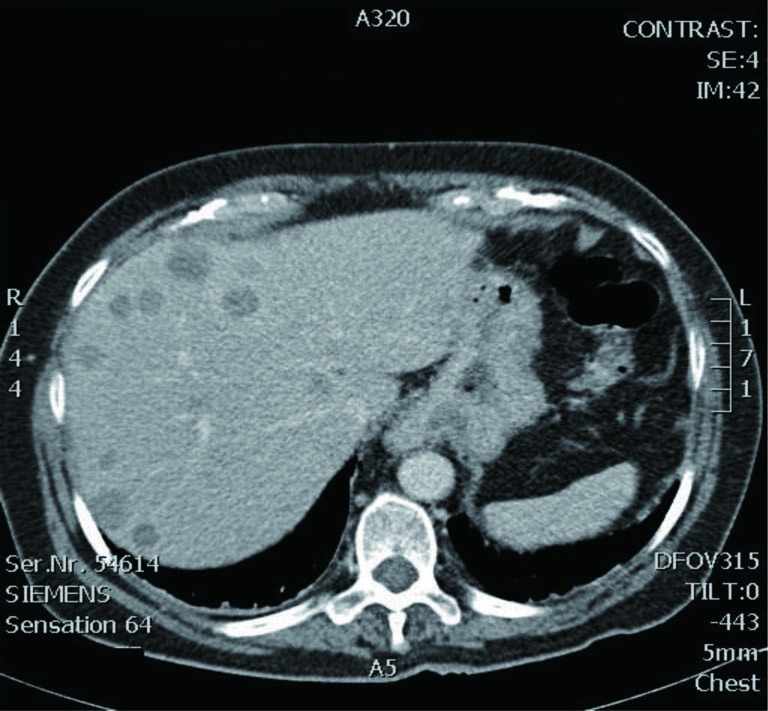

Polycystic liver disease. Red arrow. Infected hepatic cyst (Courtesy Dr. V. Penopoulos)